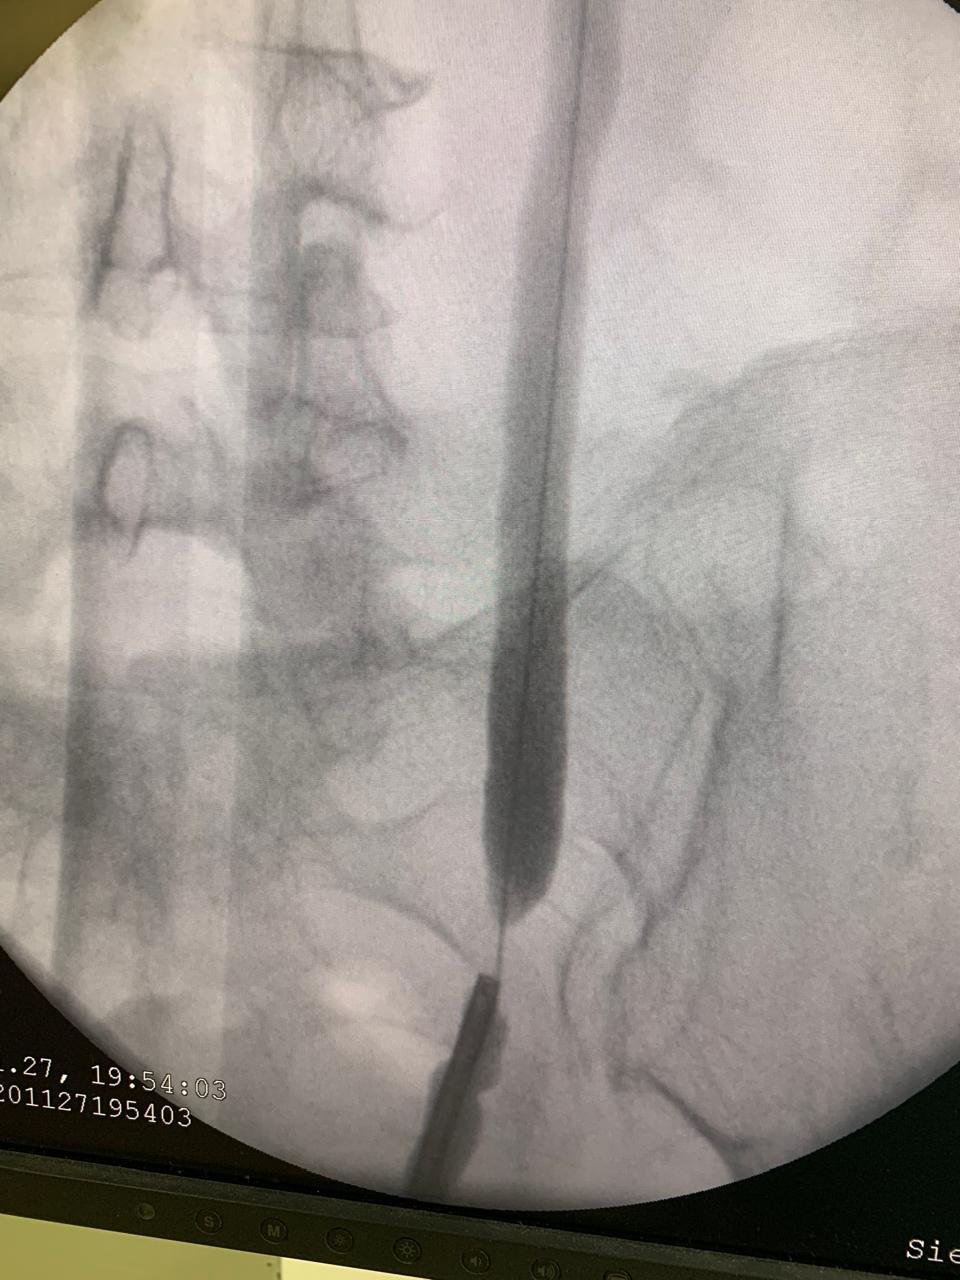

Imagem de uma radiografia mostrando a região lombar da coluna vertebral com um procedimento de injeção ou biópsia na vértebra com uma agulha.